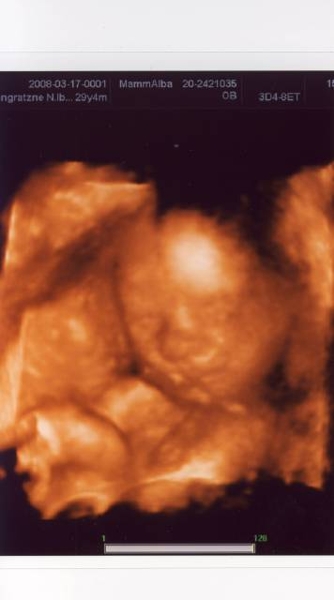

Felszerettem volna rakni egy 4D-s képet, de valahogy nemsikerül! :( Tudnátok mondani valami tippet? :)

Jó a kép, szépen látszik a kis arcocskája!

Ibi! Nagyon aranyos Gergő. Szépen kivehetőek az arcvonásai.

Tényleg csak Ronira híztál! Néztem a fényképedet és mellette Roni 4D-s képét. Nagggyon hasonlít rád! :wink: :D

Nibcsike Nagyon szép a babód! Nagyon jó kép lett!Tök jól látni az arcvonásokat már! :D